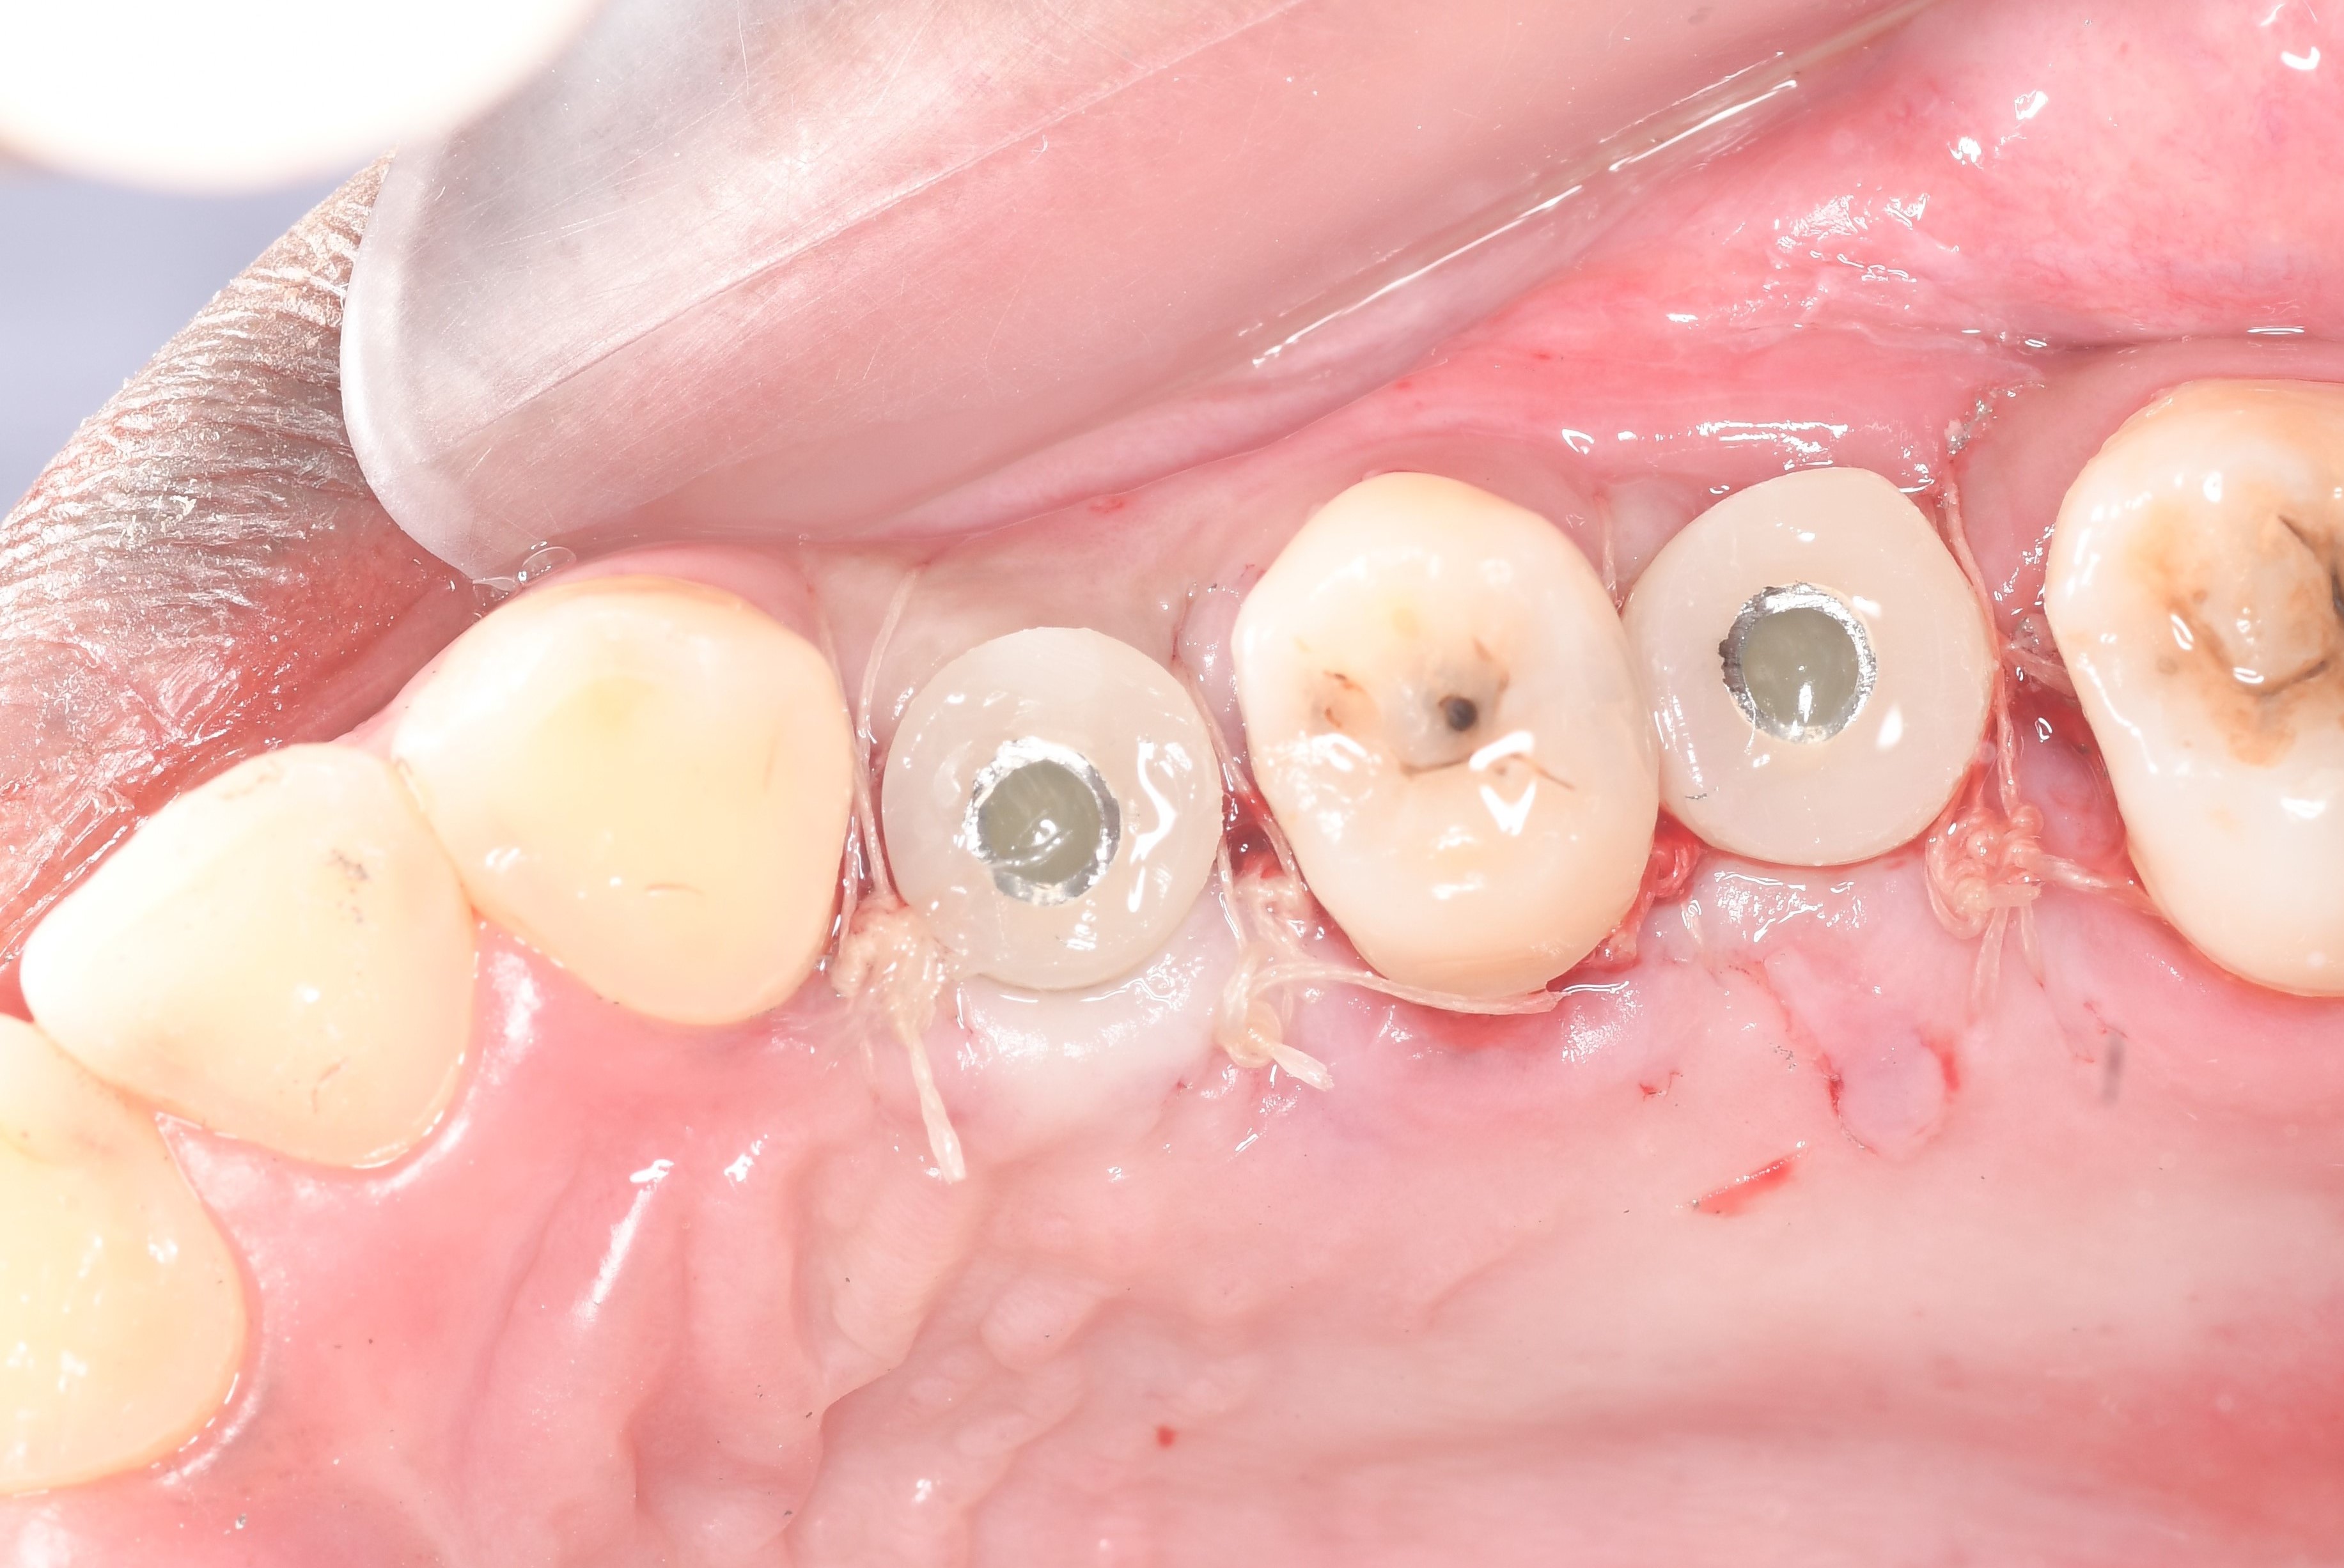

After 9 months the area is exposed in order to install the DSI classic implant and DSI temporary healing abutment